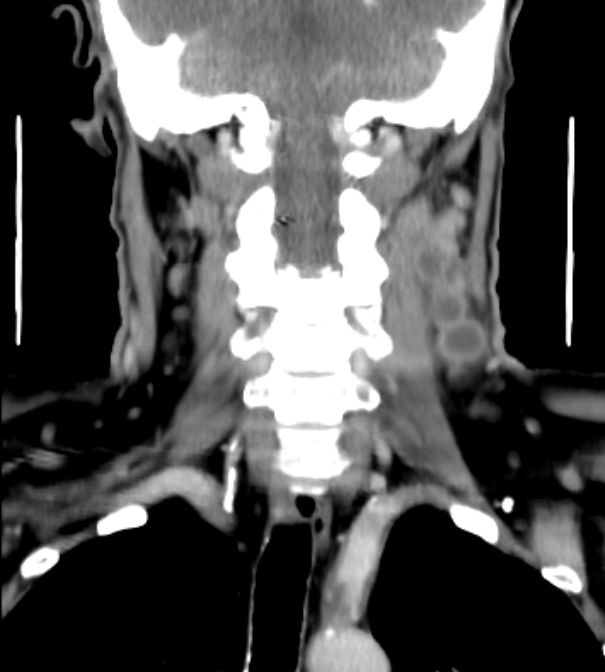

64-jähriger Mann mit tumoröser Raumforderung der linken Tonsille. Die primäre Histologie war verdächtig auf ein entdifferenziertes p16-positives Plattenepithelkarzinom. Bei der Radikaloperation wurden 84 Lymphknoten der Level 2-4 beiderseits entfernt, von denen 55 metastatisch befallenen waren. Zusätzlich wurde ein nicht zugänglicher Lymphknoten unterhalb der Karina festgestellt. Die transösophageale Punktion dieses Lymphknotens ergab den Verdacht eines malignen Lymphoms. Daraufhin wurden von den zervikalen Lymphnoten zusätzliche immunhistochemische Untersuchungen durchgeführt. Nach Vorliegen der Referenzpathologie handelt es sich um den seltenen Fall eines sarkomatoiden Lymphom oder eines histiozytischen Sarkoms. Diese Zellen sehen einem entdifferenzierten Plattenepithelkarzinom sehr ähnlich. | ||

Zahlreiche vergrößerte zervikale Lymphknoten.![]() |